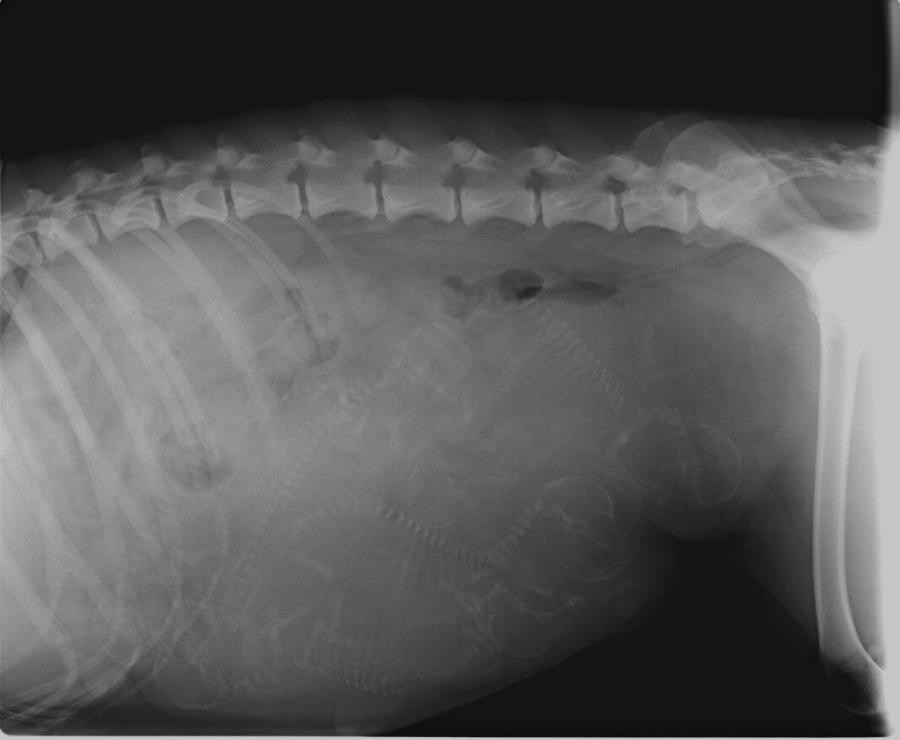

Babybauch

Röntgen 01.04.2019

Wir haben 7 Welpen gezählt!